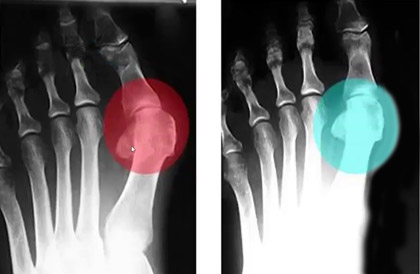

До использования

После 1,5 месяца использования шины MAGNETFIX